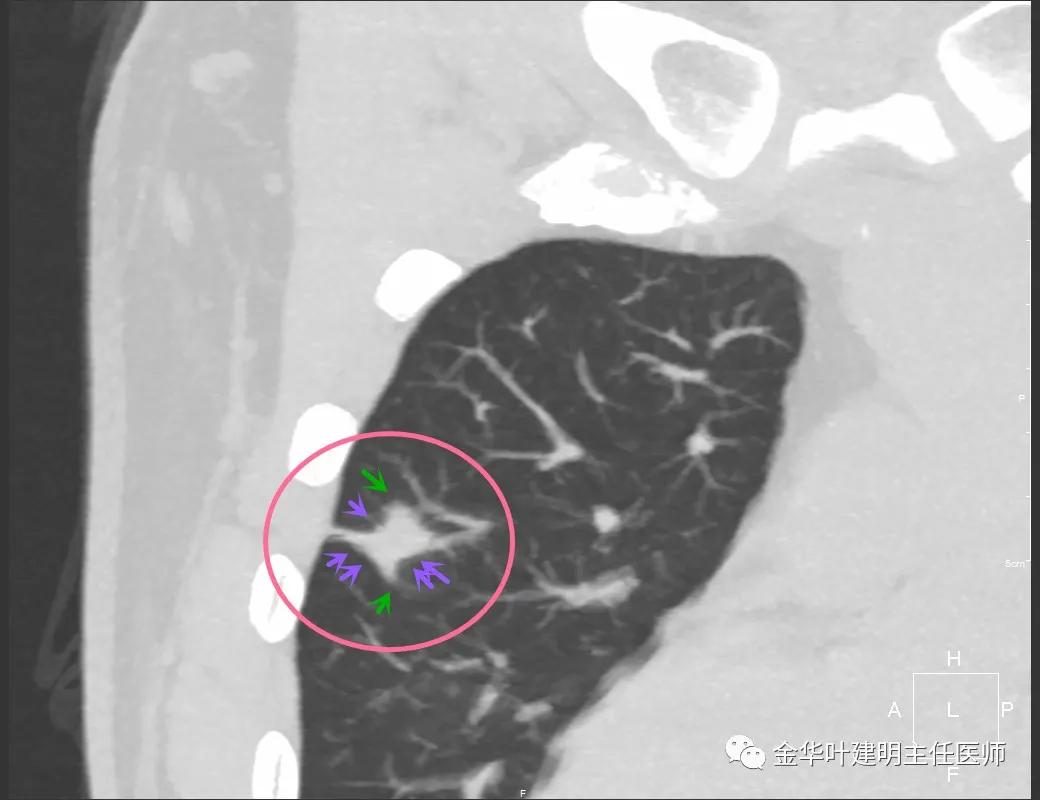

病灶实性,但收缩力弱,绿色箭头示病灶边缘有一圈晕征(模糊且均匀)

病灶实性,但收缩力弱,没有细毛刺征,实性部分比较圆润,绿色箭头示病灶边缘有一圈晕征(模糊且均匀)

紫色箭头示病灶的边缘向内凹陷,说明无膨胀性,绿色示晕征,粉色箭头指向病灶

此层面示病灶呈三角形,缺乏膨胀性,边缘较直,没有毛刺征,实性部分没有收缩纠集感,绿色箭头示晕征